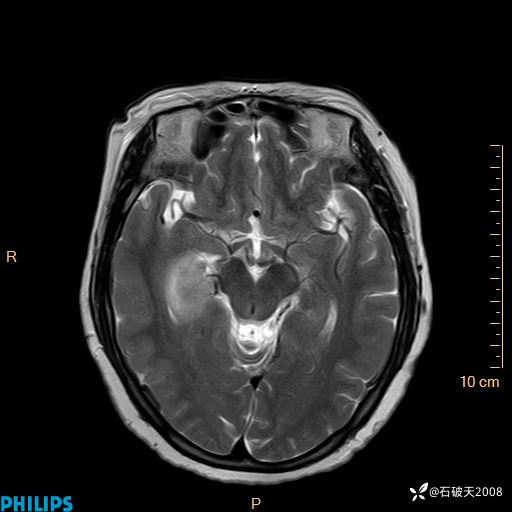

颅内占位,影像征象不是很丰富,有病理

hyy838 推荐女 62岁 主 诉:头晕12小时,加重1小时。

现病史:患者于12小时前无明显诱因出现头晕,呈持续性,无天旋地转及行走不稳,伴恶心、呕吐,呕吐共5次,呕吐物为胃内容物(具体性质不详),无胸闷、胸痛、心慌,无腹痛、腹泻,无咳嗽、咳痰,无发热、意识不清、肢体抽搐及大小便失禁等,1小时前患者上述症状加重,未诊疗,为求进一步治疗急自行来我院,门诊以“头晕待查”为诊断收入我科,发病来,神志清,精神差,饮食、睡眠差,大小便正常,体重未见明显下降。

T2